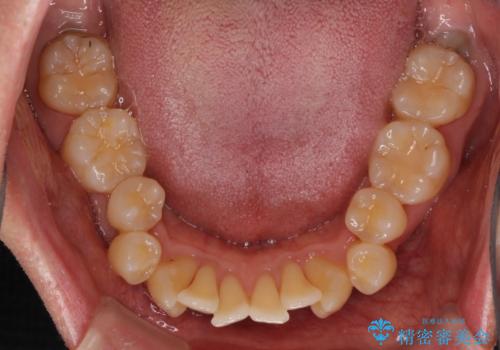

- 口元の閉じにくさと、前歯のでこぼこの歯並びを気にして来院された患者様です。

口元を積極的に引っ込めるために、上下左右の小臼歯計4本を抜歯することとしました。